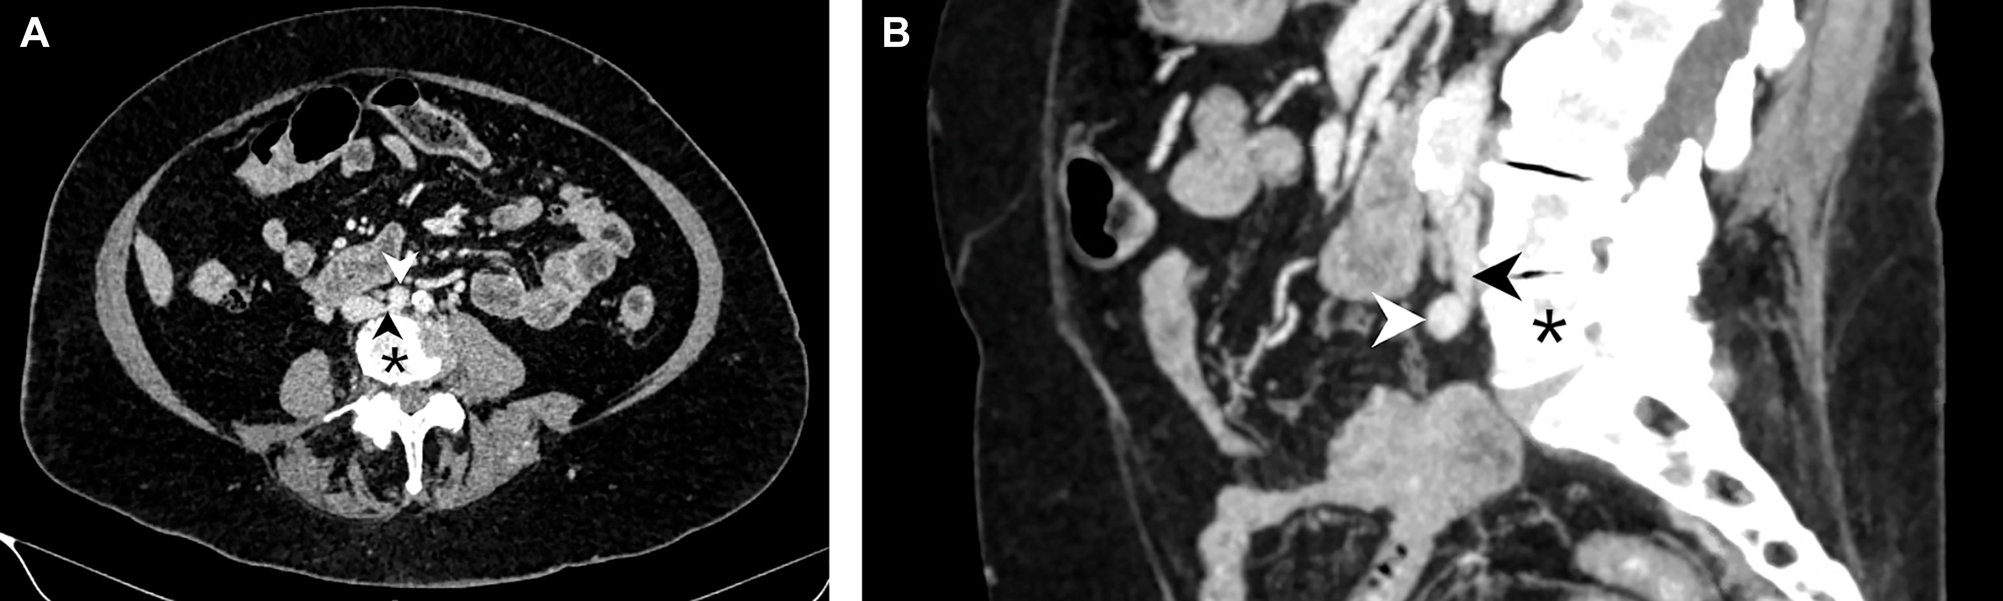

An 81 year old woman presented to the emergency department after experiencing left lower extremity swelling for four days prior. She had no associated chest pain or shortness of breath. She had a negative venous doppler ultrasound of the extremity one day earlier, but returned due to worsening pain and swelling. Physical examination revealed cyanosis and swelling extending from the left foot to the groin. Computed tomography (CT) venography revealed compression of the left common iliac vein (Images A and B, black arrowhead) between the right common iliac artery (Images A and B, white arrowhead) and the L5 vertebral body (Images A and B, black asterisk) and extensive iliofemoral deep venous thrombosis (DVT). The patient underwent mechanical thrombectomy and stenting of left common iliac vein, and she was prescribed long-term anticoagulation with apixaban. She was seen by her primary care provider five months post-presentation for her annual wellness examination and there were no residual issues. Besides the anatomic variant, no other provoking factors for DVT were identified.

May–Thurner syndrome (MTS) is an anatomic variant estimated to occur in up to 22–32% of the population [1], [2], [3]. It most commonly results from compression of the left common iliac vein between the right common iliac artery and a vertebral body [2]. MTS is a risk factor for left iliofemoral DVT which is associated with significant morbidity and mortality [4], [5], [6]. Ultrasonography has a sensitivity of 95% for proximal DVT, but has limited utility in the assessment of the inferior vena cava (IVC) and iliac veins; therefore, if iliofemoral DVT is suspected, CT or magnetic resonance venography may be considered [5]. Treatment of DVT associated with MTS is usually staged thrombolysis with or without IVC filter placement, then angioplasty with or without stenting of the left common iliac vein [7], [8], [9]. Only 5–7% of MTS-associated DVT cases receive anticoagulation alone [1], [, 10].